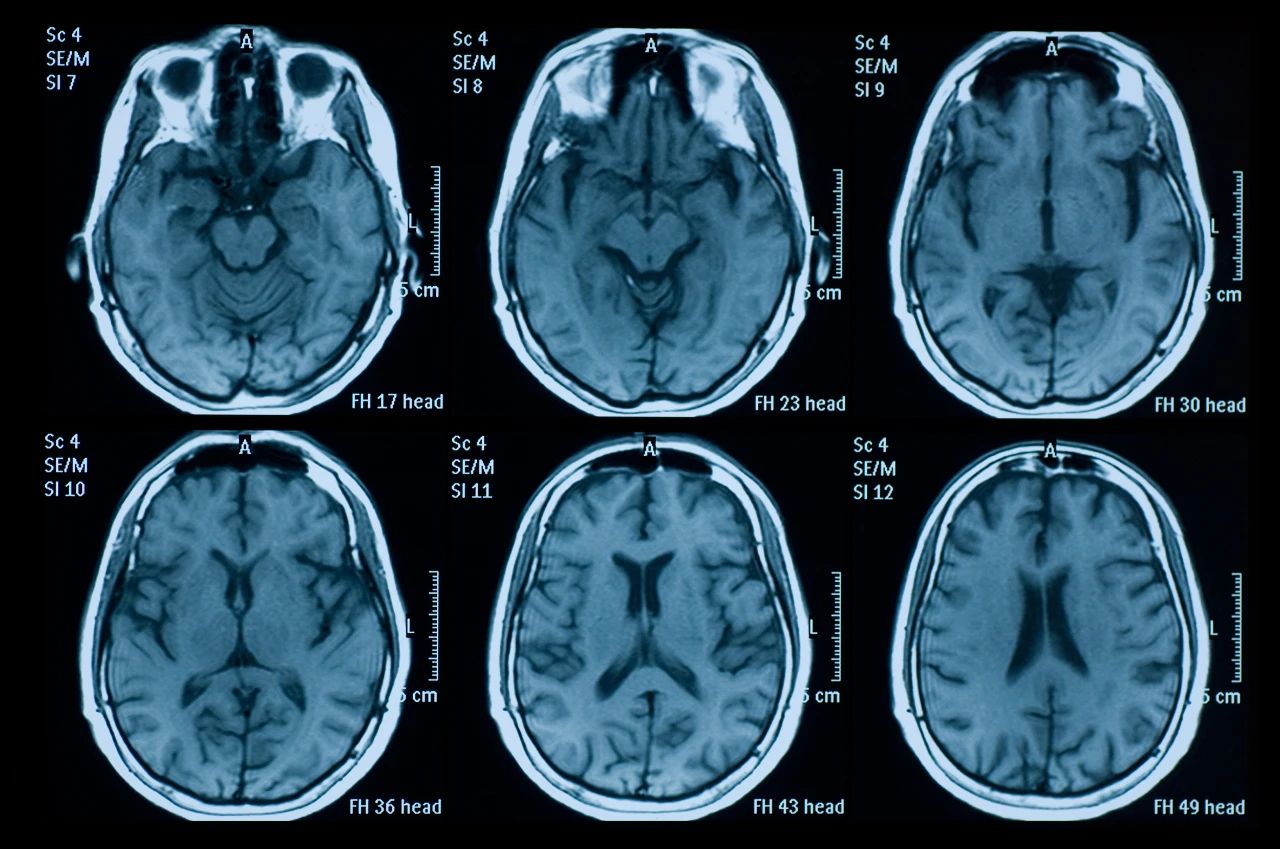

什么是創傷性腦損傷?

頭部受傷是頭部受到撞擊。它可能是輕微的,導致小腫塊或瘀傷,也可能更嚴重,導致腦損傷,如腦震蕩或腦出血。

即使您看不到頭部受傷也可能很嚴重。它們可能導致永久性殘疾或損傷,甚至死亡。更嚴重的頭部受傷總是需要去看醫生。